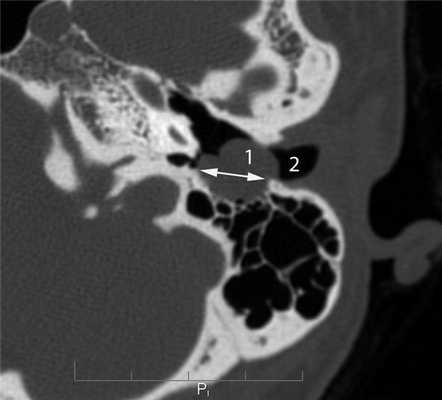

Главными отличительными признаками костной деструкции опухолевого генеза являются беспорядочность и широкая распространенность (рис. 4). Рисунок 4. Лангергансоклеточный гистиоцитоз. Аксиальная проекция правой височной кости. Распространенные беспорядочные деструктивные изменения остеолитического характера (1) в пирамиде и сосцевидном отростке. Мягкотканное образование (2) выполняет барабанную полость, обтурирует наружный слуховой проход. Участки костной деструкции могут быть выявлены на КТ в сосцевидном отростке, наружном слуховом проходе, в стенках барабанной полости и антрума, в капсуле лабиринта, в пирамиде височной кости и за ее пределами в костях основания и свода черепа [2, 4, 5]. Чем раньше обследуется ребенок с опухолью среднего уха, тем менее распространена деструкция в височной кости. Самые ранние стадии опухолевого процесса характеризуются ее отсутствием, что крайне затрудняет установление диагноза.

Другой отличительной особенностью деструкции при опухолях является литический характер, проявляющийся наличием в височной кости дефектов различной величины, значительным снижением плотности костной ткани в сочетании с неровностью и нечеткостью ее краев без явлений склероза (см. рис. 4).